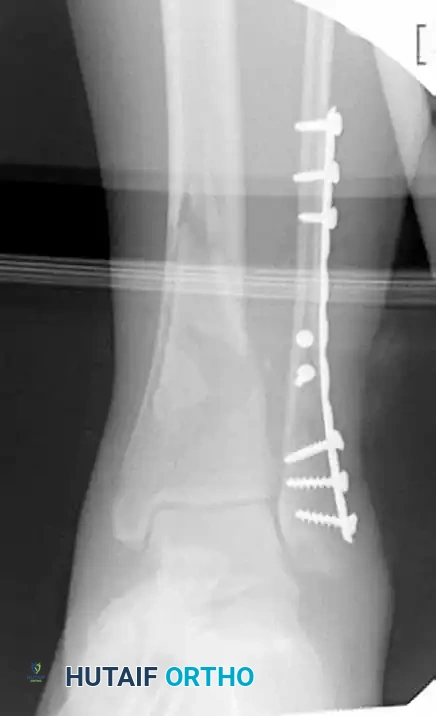

MINIMALLY INVASIVE PLATING OF TIBIAL PILON FRACTURE Surgical Diagram

Figure 54-17 F and G: Final postoperative AP and Lateral radiographs demonstrating excellent restoration of the articular surface and stable bridge plating of the metadiaphysis.